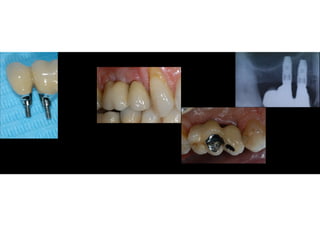

The document discusses digital workflow for making proper abutments when dental fixtures are placed close together. It outlines the treatment planning process, including CBCT scanning and surgical guides. There are two types of abutments: traditional pre-made abutments and digitally customized abutments made through CAD/CAM. Digital workflow allows visualization of contacts, non-contacts, and pressure points before and after extraction and placement of fixtures to determine the best type of final prosthesis.